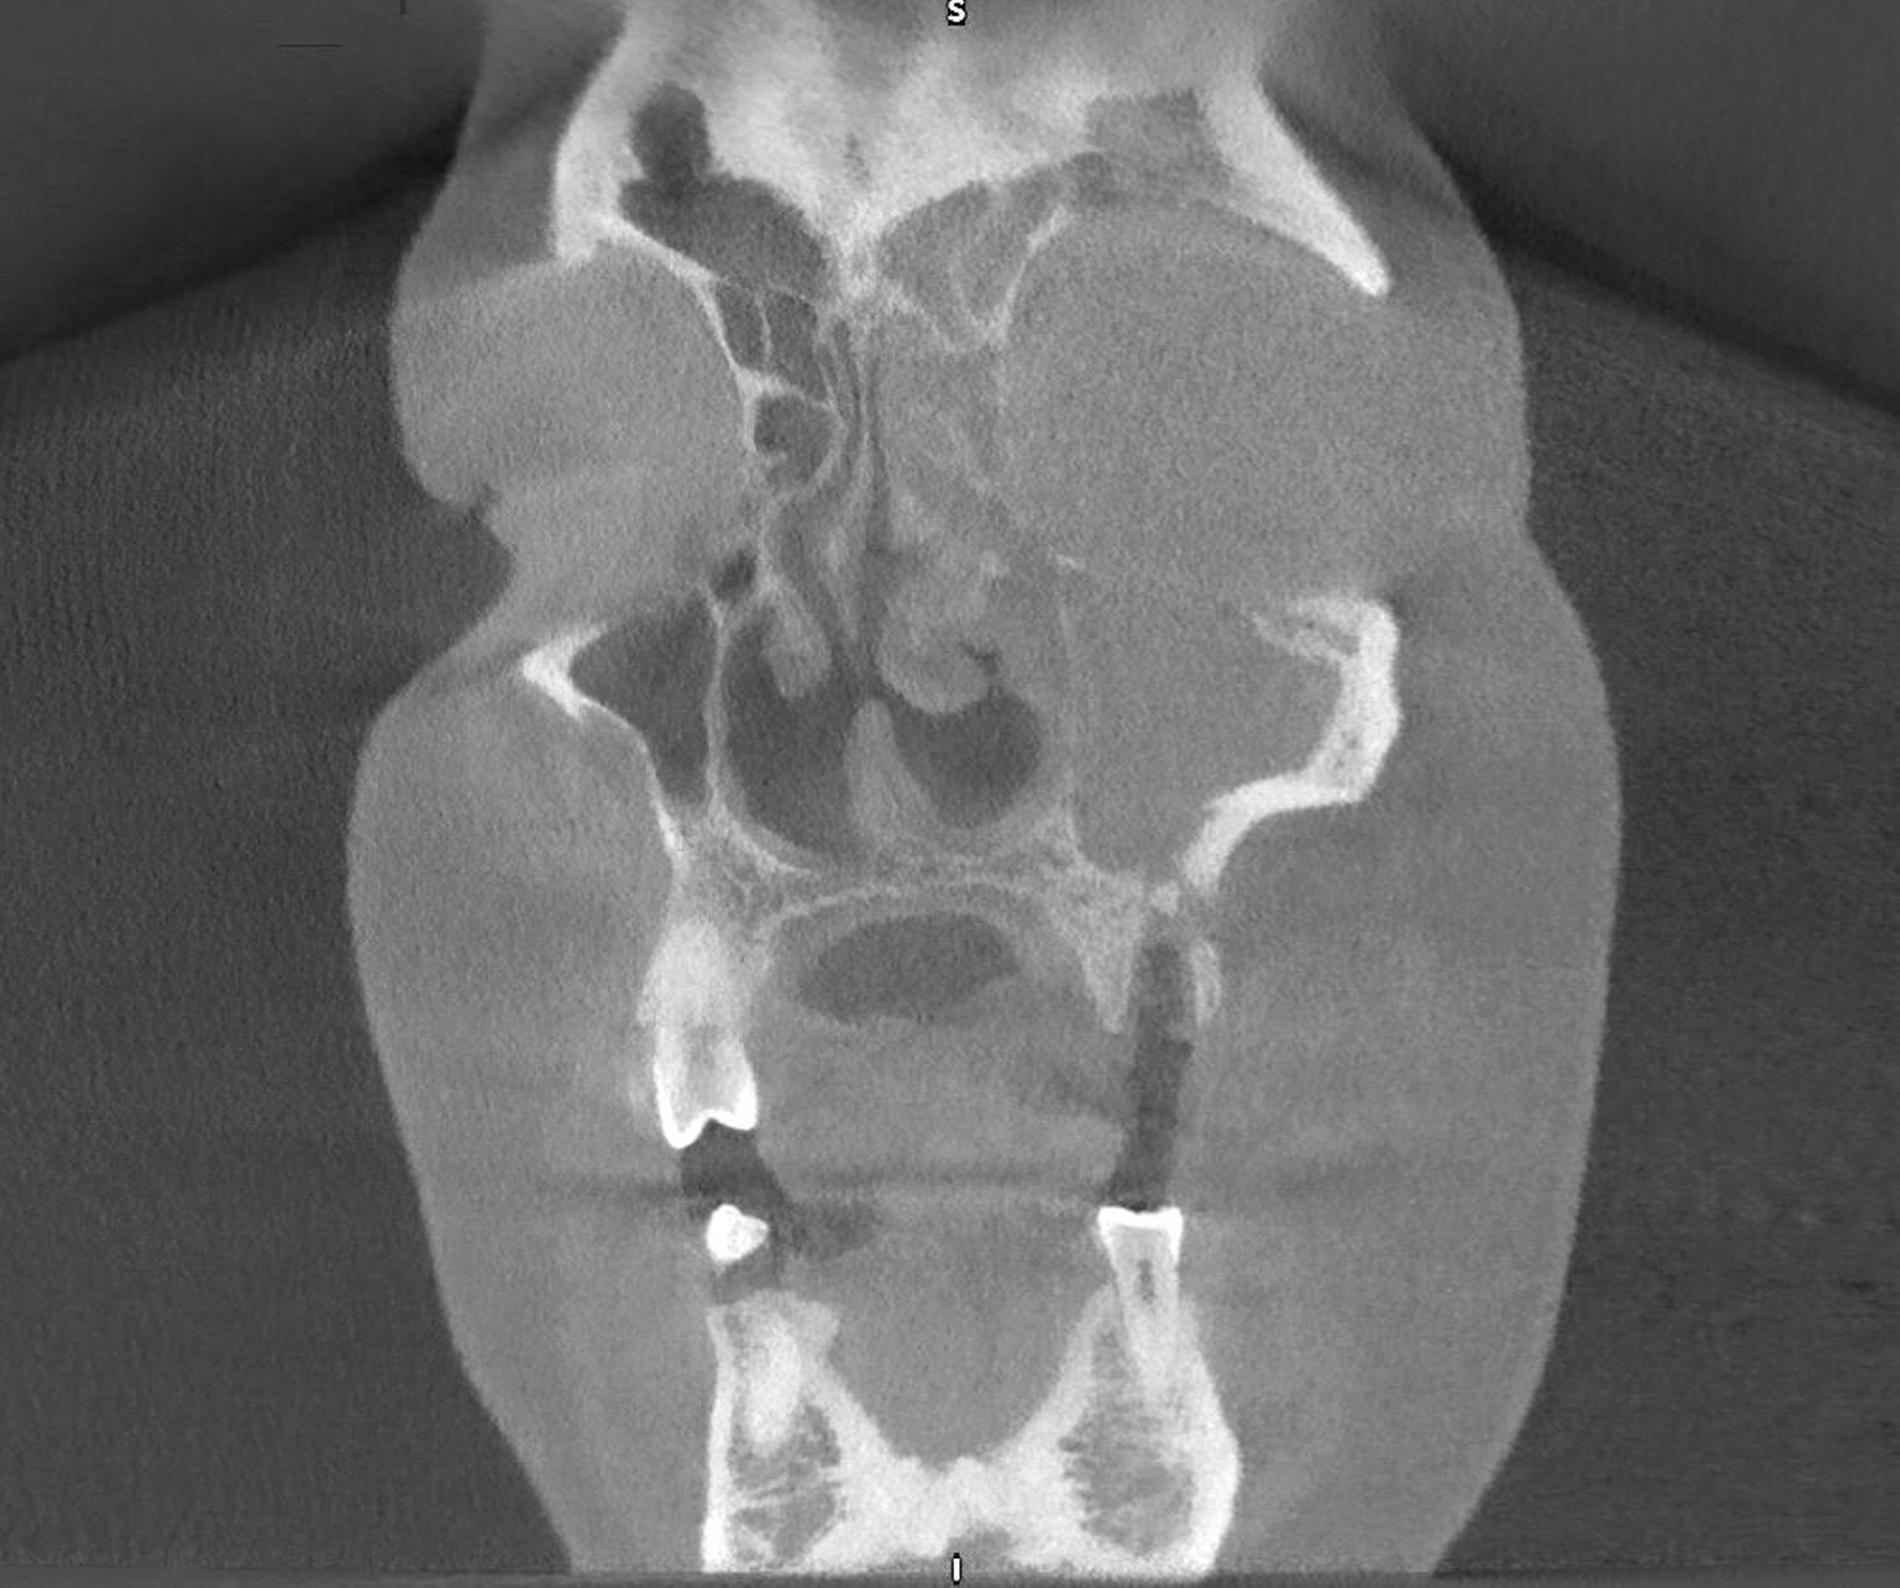

Aus diesem Grund wurde bereits nach der ersten klinischen Befundaufnahme ein Notfall-CT mit Kontrastmittel angemeldet, ein augenärztliches Konsil gestellt und der diensthabende HNO-Kollege konsiliarisch hinzugezogen. Zwischenzeitlich war ein DVT durchgeführt worden, das einen Wurzelrest 25 als offensichtliche Ursache der odontogenen Sinusitis maxillaris zeigte, die sich zudem auf Siebbein und Stirnhöhle ausgedehnt hatte (Abbildung 4).

Im Unterschied zur DVT zeigte die Computertomografie mit Kontrastmittel einen medial lokalisierten subperiostalen Abszess in der linken Orbita mit umgebender entzündlicher Gewebereaktion, gedeutet als zumindest umschriebene Phlegmone (Abbildung 6). Die augenärztliche Untersuchung ergab einen Visus rechts von 1,0 und links von 0,63.